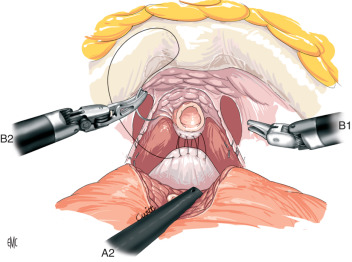

PROSTATECTOMIA ROBÓTICA

A PROSTATECTOMIA ROBÓTICA é uma técnica moderna e minimamente invasiva que utiliza uma plataforma robótica para melhorar a qualidade e precisão da cirurgia